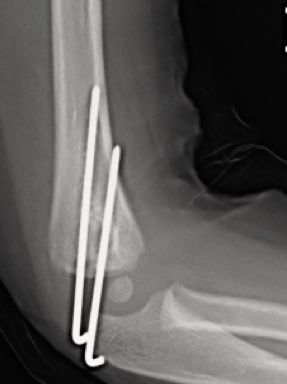

A menudo las radiografías convencionales, anteroposterior y lateral de codo, pueden infravalorar el desplazamiento real, por lo que se recomienda la realización de una proyección oblicua si fuera necesario, siendo ésta, la que mejor valora el desplazamiento. La línea de fractura va desde la superficie articular hasta la metáfisis distal del húmero. Las fracturas no desplazadas o mínimamente desplazadas (<2 mm) con integridad de la superficie articular se pueden tratar de forma conservadora mediante férula braquial y controles periódicos para valorar un posible desplazamiento secundario. Las fracturas desplazadas (>2 mm) precisan tratamiento quirúrgico. Si existe una afectación del cartílago articular, (evidenciado por RM o artrografía, está indicada la reducción abierta y estabilización con agujas de Kirschner (Figura 8). Una disección cuidadosa, respetando la zona posterior del cóndilo minimizará los riesgos de necrosis avascular del cóndilo humeral. Si la superficie articular está intacta, la reducción cerrada y estabilización con agujas de Kirschner es suficiente. La reducción anatómica de la superficie articular se realizará gracias a la visualización directa. En ocasiones, es difícil la reducción y la dorsiflexión de muñeca, relajando los músculos dorsiflexores, facilitará la reducción. La osteosíntesis se realizará con dos agujas de Kirschner lisas, con el punto de entrada posterior a la incisión y colocadas de forma paralela o divergente. A diferencia de las fracturas supracondíleas, en las que 3-4 semanas de inmovilización es suficiente, la inmovilización de las fracturas del cóndilo deben mantenerse por lo menos durante 4 semanas para evitar el riesgo de pseudoartrosis. Las agujas de Kirschner no se deben retirar hasta comprobar signos radiológicos de consolidación. Es importante informar a los padres de la posibilidad de aparición de una prominencia lateral, a menudo confundida con un cúbito varo, provocada por el hipercrecimiento óseo asociado a la atrofia de la musculatura. La rigidez articular es más frecuente que en las fracturas supracondíleas. La utilización de férulas dinámicas disminuye el riesgo de esta complicación.

Figura 8: a-d, Imagen radiografica de fractura del cóndilo lateral con desplazamiento articular. Tratamiento quirúrgico mediante reducción abierta y osteosíntesis.